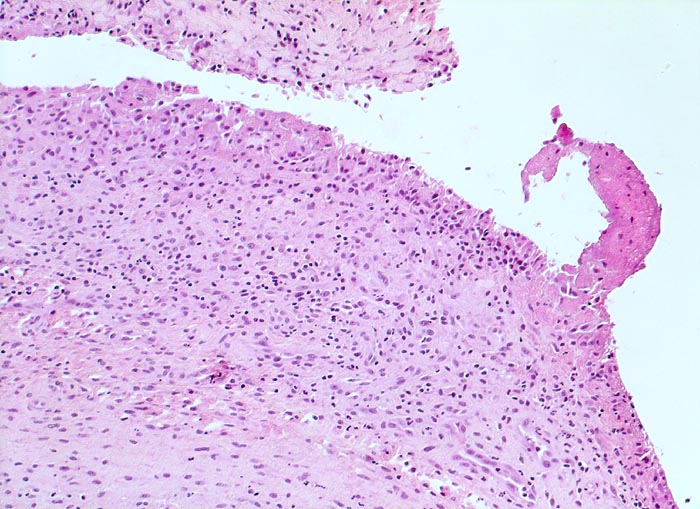

In Abhängigkeit von der Entzündungsdauer werden unterschiedliche morphologische Befunde beschrieben. Die initiale proliferative Phase ist charakterisiert durch eine Hyperplasie der Synovialis, Fibrinexsudate und Gelenkergüsse. In der destruktiven Phase kommt es zur Zerstörung von Gelenkknorpel und gelenknahem Knochen durch Ausbildung eines intraartikulären Pannusgewebes (> 194). Die ausgebrannte Phase ist gekennzeichnet durch eine synoviale Fibrose mit zunehmender Ankylose (= Gelenkversteifung).

Typische histologische Veränderungen sind eine synoviale Zottenhyperplasie, Verbreiterung der Deckzellschicht unter Einschluss mehrkerniger Riesenzellen, Fibrinexsudate und synoviale Ulzerationen, Infiltrate von Lymphozyten teils in Form von Lymphfollikeln, Plasmazellen, neutrophilen Granulozyten, Makrophagen und Siderophagen, sowie Einschlüsse von Knorpel- und Knochenfragmenten (Detritussynovialitis). Die histologischen Befunde der Synovialis korrelieren oft nicht mit den klinischen Angaben. Trotz fortgeschrittener Gelenkdestruktion mit ausgeprägter klinischer Symptomatik können Synovialektomiepräparate nur sehr geringe pathologische Veränderungen zeigen. Oft ist auch nicht mehr zu eruieren, welche Läsionen Folge der Grundkrankheit und welche Folge diverser intraartikulärer Therapien oder begleitender Superinfektionen sind.

• Synovialis mit verplumpten Zotten.

• Stark proliferierte mehrreihige synoviale Deckzellschicht.

• Herdförmig Fibrinauflagerungen durchsetzt von neutrophilen Granulozyten.

• Hyperzelluläres Stroma mit lymphoplasmazellulärem Entzündungsinfiltrat mit Ausbildung von Lymphfollikeln.